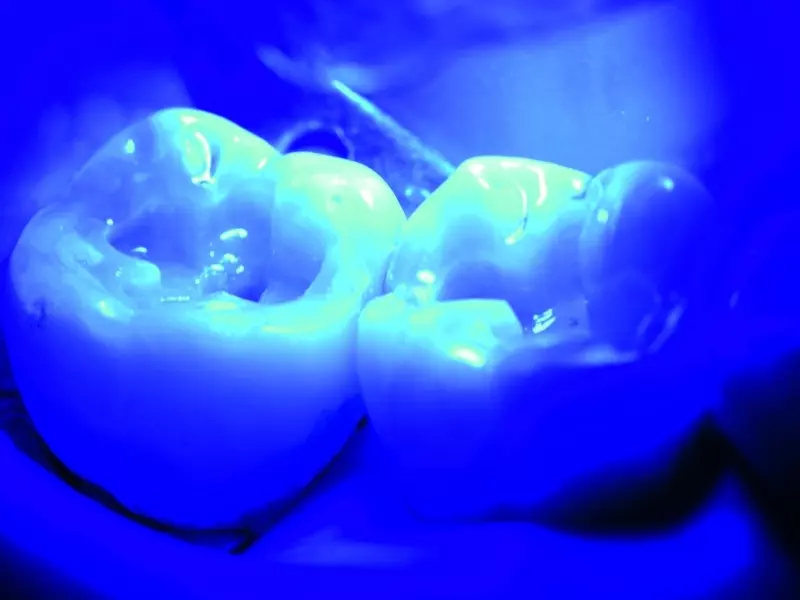

Po założeniu koferdamu usunięto wypełnienia i opracowano ubytki (zdj. 2). Po usunięciu wypełnień widać było wyraźnie, że doszło do rozwoju próchnicy wtórnej (zdj. 3). W efekcie powstały rozległe i głębokie ubytki (zdj. 4). W tej sytuacji zdecydowano się na wykonanie bezpośredniej odbudowy, używając kompozytu o niskim skurczu i dużej głębi polimeryzacji. To uprościło i przyspieszyło leczenie, gwarantując zarazem zachowanie wysokiej jakości wypełnień. Zdecydowaliśmy się na użycie materiału Admira Fusion x-tra (VOCO).

Najpierw zmierzono ubytki sondą z milimetrową podziałką i stwierdzono, że w najgłębszym miejscu nie przekraczały one 4 mm. Zastosowano samotrawiący system łączący Futurabond DC (zdj. 5), który następnie polimeryzowano światłem przez 10 sekund (zdj. 6).